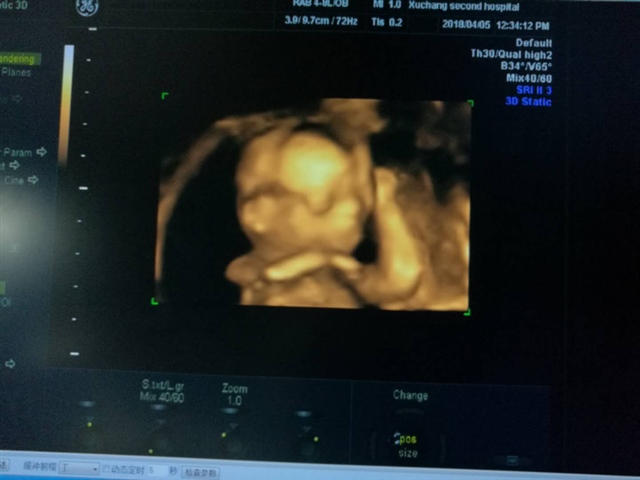

孕29周+5天

孕27周+1天